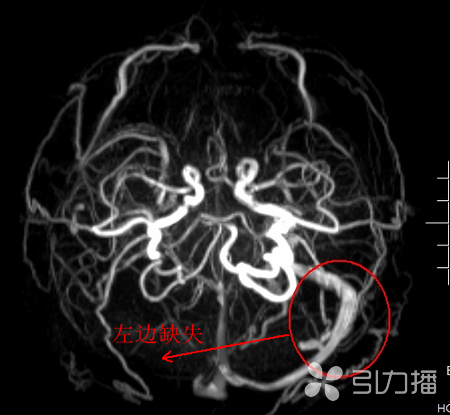

医生觉得胡先生的头痛没有那么简单,建议胡先生拍一个头颅CT。CT结果提示胡先生右侧横窦密度较高,医生建议立即住院作进一步检查。住院当天,病房医生联系影像科为胡先生加急做了磁共振检查,结果出人意料,胡先生被诊断为静脉窦血栓形成,就是脑袋里有一根主要的静脉堵塞了!医生立即给予抗凝治疗,目前胡先生头痛已经好多了,病情也稳定了。